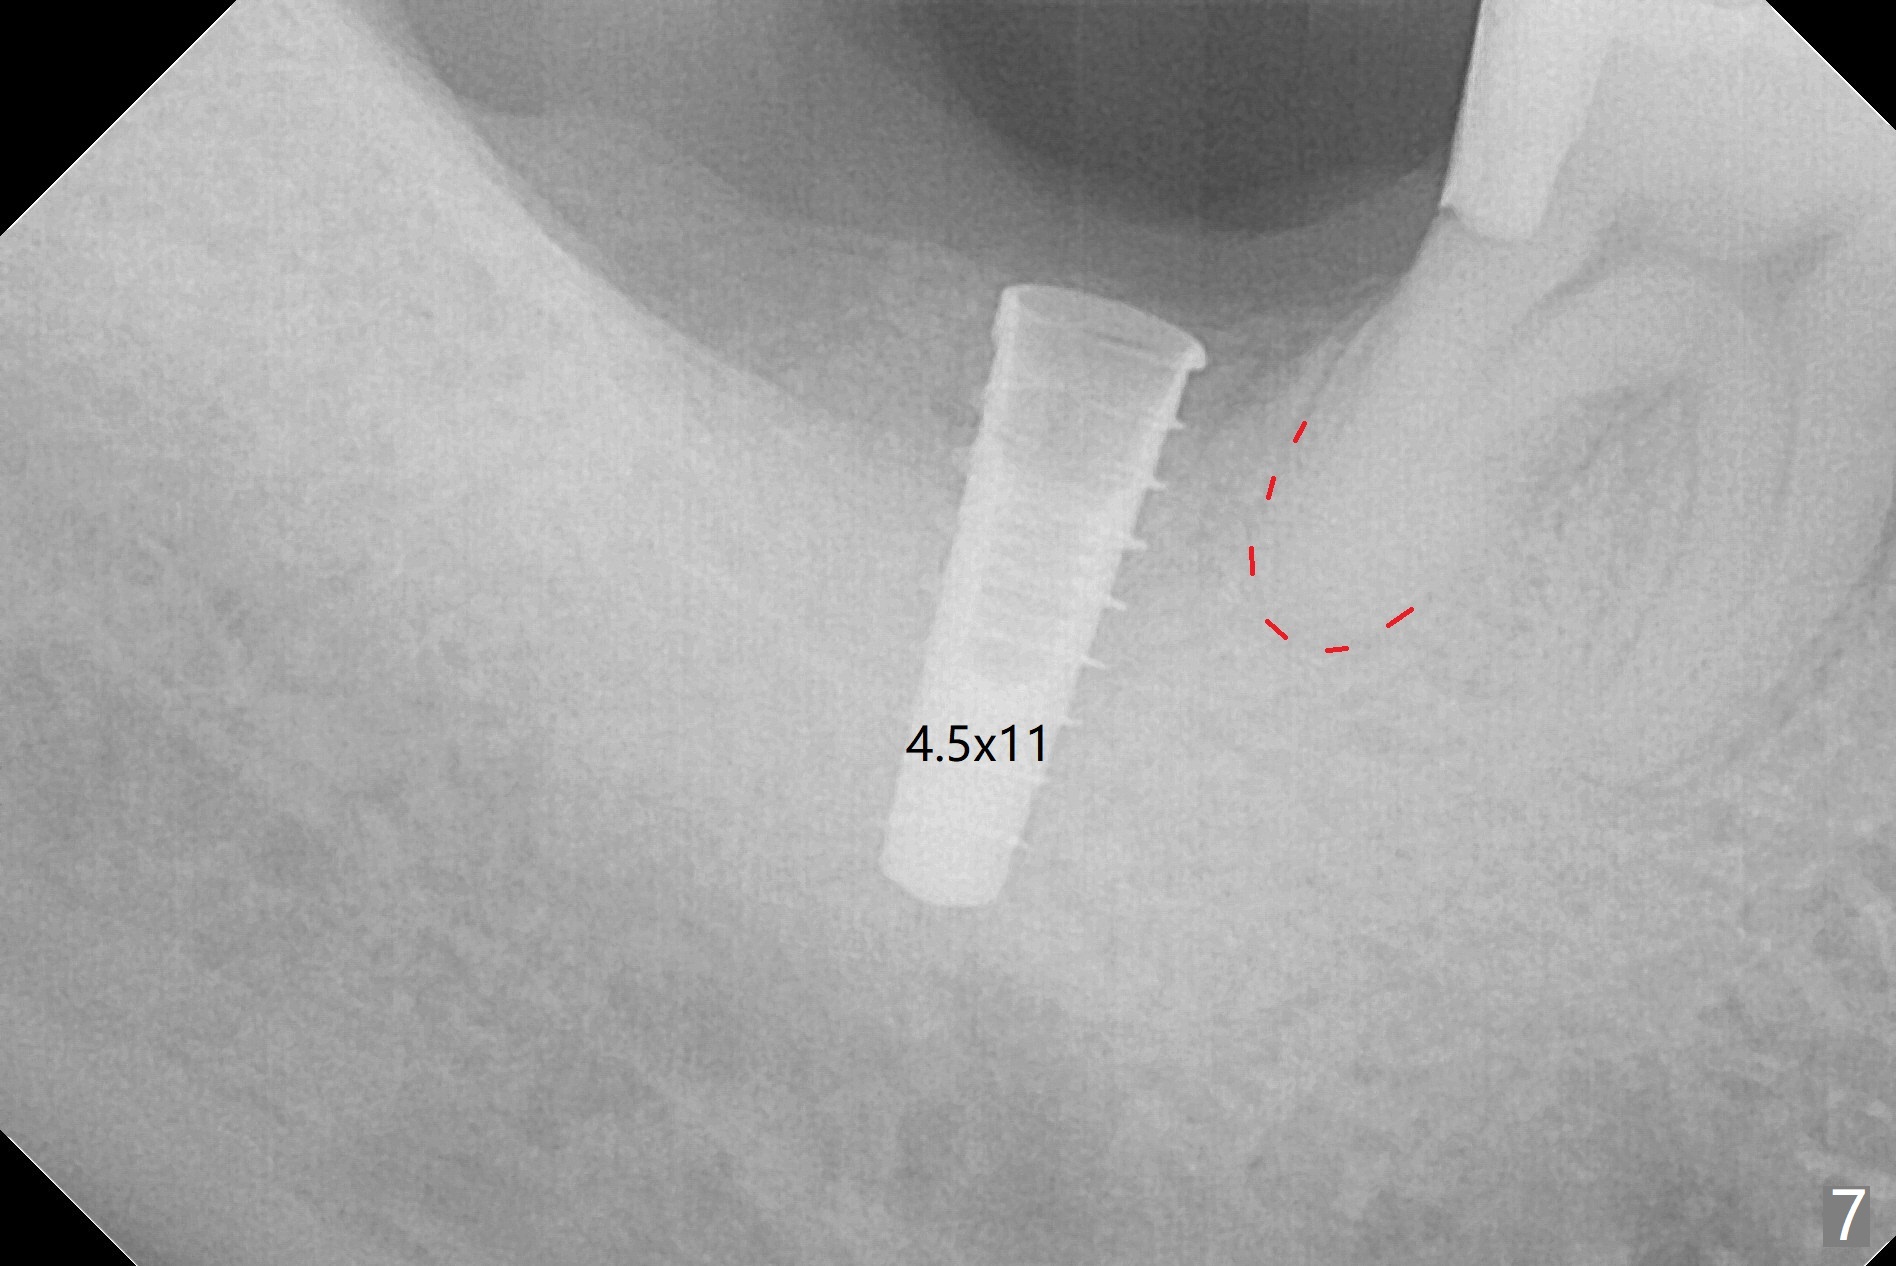

The socket shrinks with buccal plate reduction 3 months post socket preservation (Fig.5), as compared to 10 days postop (Fig.4). To restore the socket as much as possible, Magic Split is used (flapless), followed by Magic Expanders 3-3.8 mm for 11 mm (gingival level) and a 4x11mm dummy implant (Fig.6). The osteotomy is moved distal by using Lindamann bur; following 3.8 mm Magic Drill, a 4.5x11 mm dummy implant (Fig.7). Finally a definitive 5.5x9 mm implant is placed with <45 Ncm; a 6x2 mm healing abutment is placed to close the access (Fig.8). Autogenous bone harvested from the Magic Drill returns to the osteotomy mainly buccal prior to implant placement (Fig.8 *). The patient reports no discomfort immediately postop, thanks to the flapless technique. The patient has had postop pain; 11 days postop, the abutment and implant are found to be loose. After re-tightening by hand, the complex is seated deeper and more stable (Fig.9 arrow).